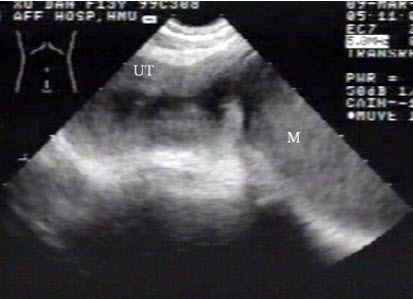

女,16岁,有性生活史,因停经35天。根据B超检查声像图如下,合理的超声诊断意见为()

A.动态观察

B.早孕

C.宫外孕可能,建议经阴道超声检查

D.抗感染治疗

E.内膜过度增生